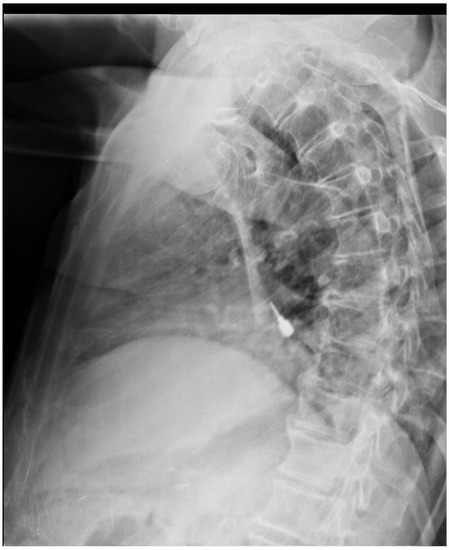

A 78-year-old Caucasian male with primary degenerative dementia (Alzheimer’s disease), who was treated with Memantine, Quetiapine, and Haloperidol sought treatment for difficulty in chewing. The patient complained about other comorbid medical conditions that also required numerous medications, such as, Allopurinol, Simvastatin, baby Aspirin, a mixture of ethyl esters of polyunsaturated fatty acids, and the association between Telmisartan and Hydrochlorothiazide. The patient had a fixed dental prosthesis supported by dental implants, delivered many years before. In recent years, with the increase in difficulty of carrying out oral hygiene procedures, the implants had developed peri-implantitis (Figure 1). The treatment plan was to remove three implants and to retain the others, in order to fabricate a removable denture with implant retention. However, during the dental procedure, it was assumed that the patient swallowed a small screwdriver (Figure 2) due to a sudden unconscious movement. The screwdriver was not tethered to a dental floss, the clinician thought that was not necessary because the procedure involved only the anterior teeth.

Figure 1. A panoramic radiograph showing evident peri-implantitis in lower jaw.